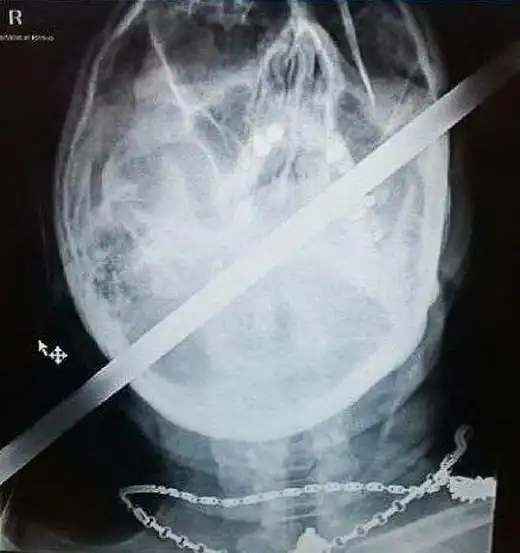

Металлический стержень проткнул голову байкера насквозь

Одному везучему байкеру кусок арматуры при аварии проткнул голову насквозь. Ни один жизненно важный орган не был задет. После больницы, где посторонний предмет ловко извлекли, он катается и дальше.